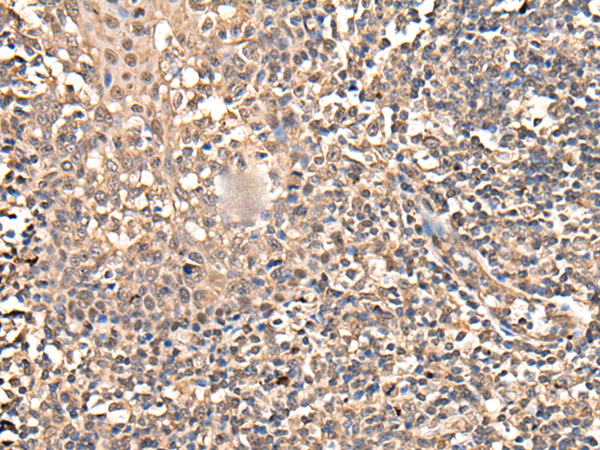

分类: 科研抗体货号: P09349别名: G5; BAT4; D6S54E; ANKRD59; GPATCH10应用: IHC反应种属: Human, Mouse